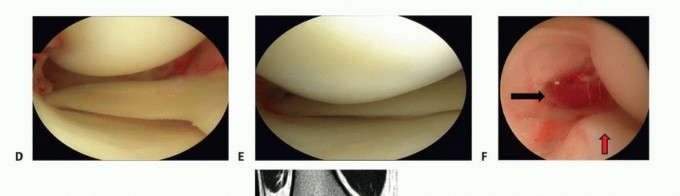

FIG 1 • A. Pellegrini-Stieda lesion indicating chronic MCL insufficiency. B. Arthroscopic ipsilateral medial

drive-through sign. The joint space opens more than 10 mm and permits complete passage of the arthroscope into the back of the medial compartment. C. The arthroscopic examination permits direct evaluation of the injured structure, including the POL and tibial- or femoral-sided deep MCL. The meniscus tends to follow the noninjured structure. A proximal meniscal lift-off suggests a tibial-sided tear, whereas a distal lift-off suggests a femoral-sided tear. (continued)

An ipsilateral “drive-through” sign (ie, opening of the medial compartment of more than 10 mm, allowing for complete insertion of the arthroscope into the medial compartment [FIG 1B]) should arouse suspicion for a significant MCL injury that may require repair or reconstruction. If one can see easily the entire medial meniscus posterior horn, then you have significant medial opening. If the meniscus follows the femur, you have a tibial-sided lesion; if the meniscus stays with the tibia and the gap is above the meniscus, you have a femoralsided lesion.

The location of the acute or chronic injury—femoral or tibial—also can be evaluated. Separate injuries of the POL also can be visualized (FIG 1C-F*).

FIG 1 • (continued)D. Additional image of arthroscopic ipsilateral medial drive-through sign. E. Post-MCL fixation, medial drive-through has been eliminated. F. Seventy-degree scope in Gillquist position with nice view of torn POL (black arrow). Medial meniscus (red arrow). G. Suture repair, from outside in, of the POL. H. Tibial-sided avulsion of MCL into the knee joint.